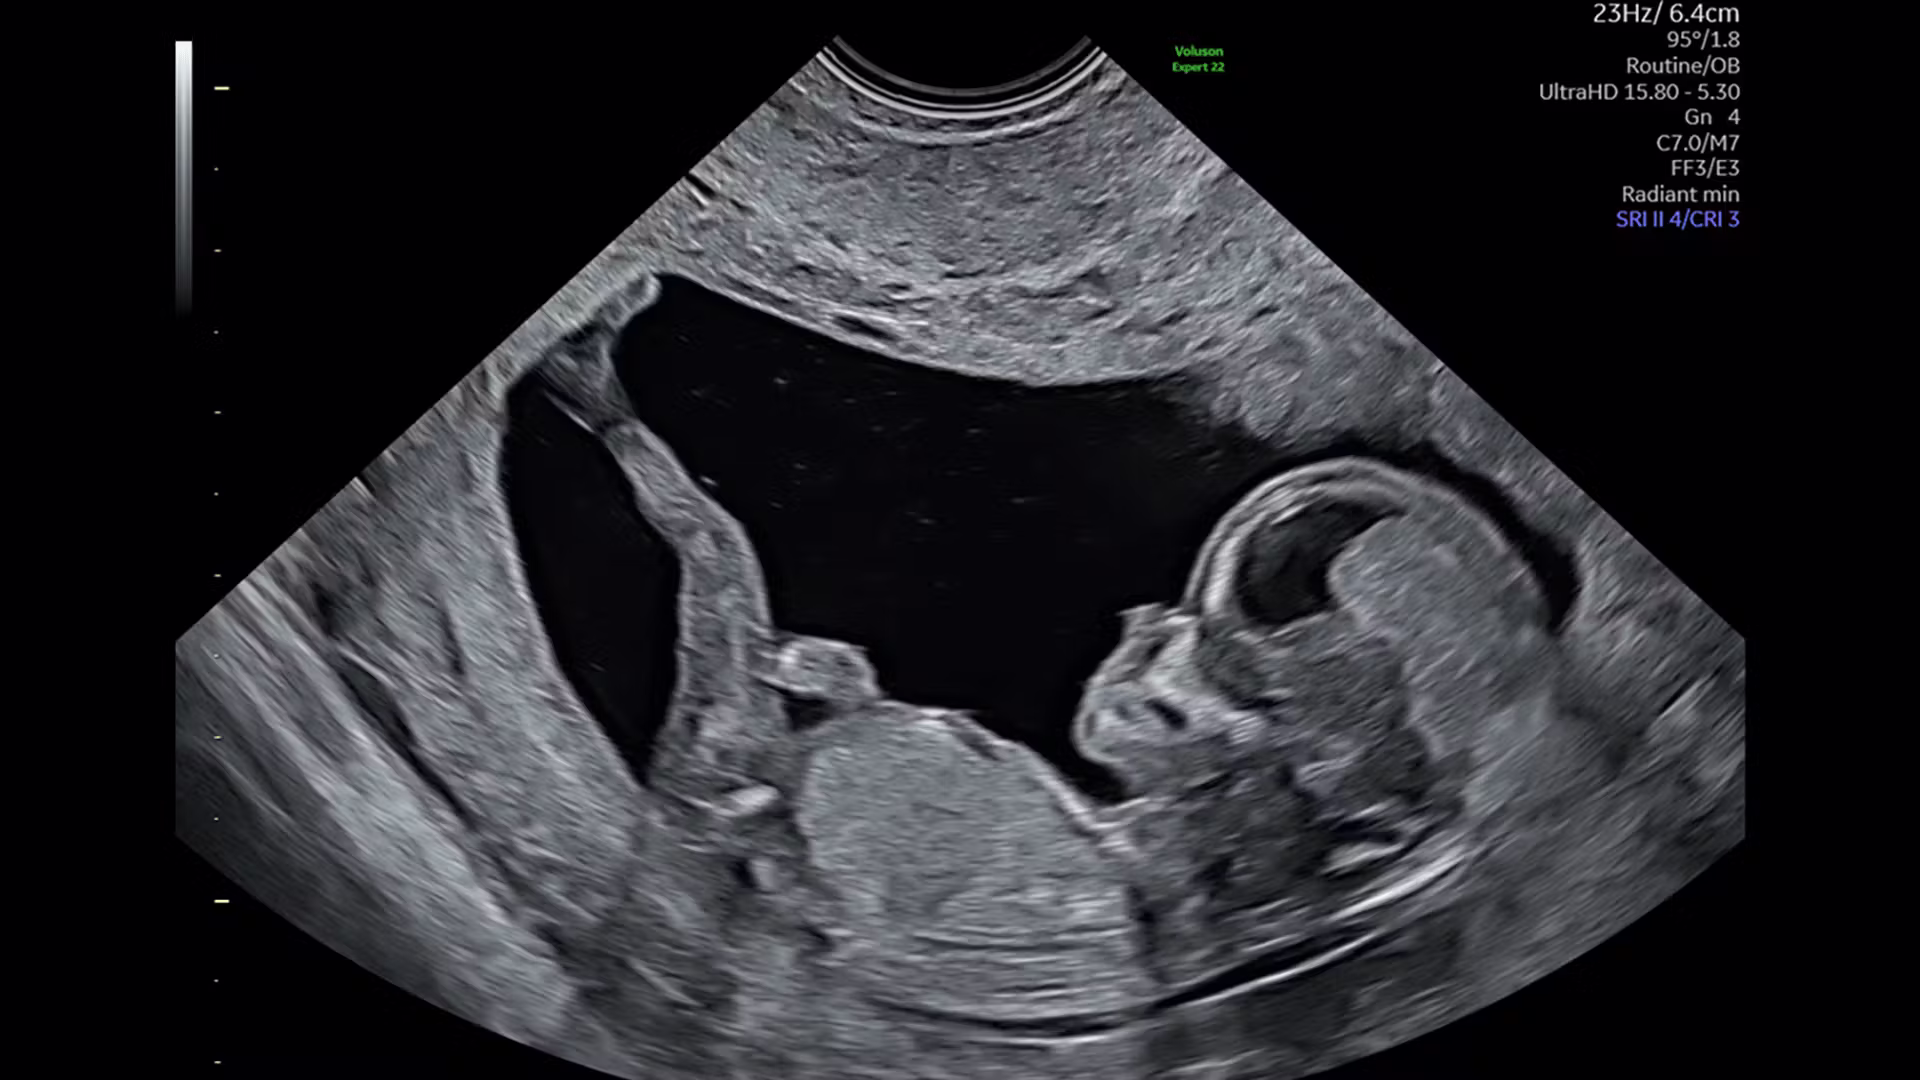

Cea mai importantă ecografie morfologică este cea din trimestrul II, realizată de obicei între 20 și 24 de săptămâni de sarcină. În acest moment, organele copilului sunt suficient de dezvoltate pentru a putea fi analizate în detaliu, iar majoritatea malformațiilor structurale pot fi identificate.

În timpul morfologiei fetale, medicul specialist efectuează o evaluare sistematică a corpului fetal. Aceasta presupune analizarea structurii creierului, a coloanei vertebrale și a feței copilului, dar și examinarea organelor interne precum inima, plămânii, stomacul și rinichii.

Un element foarte important al examinării îl reprezintă evaluarea inimii fetale, deoarece malformațiile cardiace sunt printre cele mai frecvente anomalii congenitale. De asemenea, medicul analizează membrele copilului și modul în care acestea se dezvoltă.

Pe lângă anatomia fetală, sunt evaluate și alte elemente esențiale pentru evoluția sarcinii, precum poziția placentei, cantitatea de lichid amniotic și fluxurile sanguine din circulația fetoplacentară.

Tehnologia modernă permite realizarea ecografiilor tridimensionale și 4D, care oferă imagini mult mai detaliate ale fătului. Aceste metode pot fi utile în evaluarea anumitor structuri anatomice, în special la nivelul feței sau al membrelor.